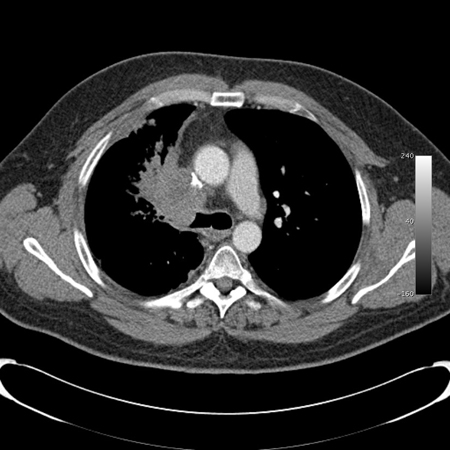

Malignant endobronchial obstruction on multidetector chest CT: mediastinal window demonstrating right mainstem malignant obstruction

From the collections of Jose Fernando Santacruz MD, FCCP, DAABIP and Erik Folch MD, MSc; used with permission